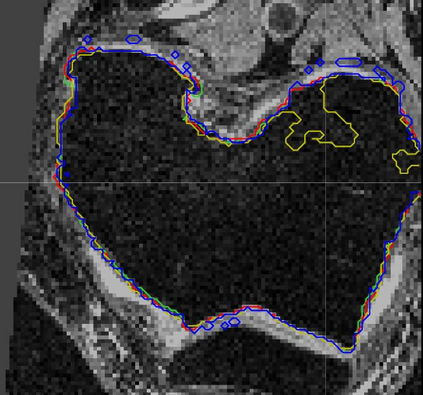

Direct automatic segmentation of objects from 3D medical imaging, such as magnetic resonance (MR) imaging, is challenging as it often involves accurately identifying a number of individual objects with complex geometries within a large volume under investigation. To address these challenges, most deep learning approaches typically enhance their learning capability by substantially increasing the complexity or the number of trainable parameters within their models. Consequently, these models generally require long inference time on standard workstations operating clinical MR systems and are restricted to high-performance computing hardware due to their large memory requirement. Further, to fit 3D dataset through these large models using limited computer memory, trade-off techniques such as patch-wise training are often used which sacrifice the fine-scale geometric information from input images which could be clinically significant for diagnostic purposes. To address these challenges, we present a compact convolutional neural network with a shallow memory footprint to efficiently reduce the number of model parameters required for state-of-art performance. This is critical for practical employment as most clinical environments only have low-end hardware with limited computing power and memory. The proposed network can maintain data integrity by directly processing large full-size 3D input volumes with no patches required and significantly reduces the computational time required for both training and inference. We also propose a novel loss function with extra shape constraint to improve the accuracy for imbalanced classes in 3D MR images.

翻译:3D医学成像的物体,如磁共振成像(MR)成像的直接自动分离,具有挑战性,因为往往需要精确地确定大量调查中大量存在复杂地理不对称的单个物体。为了应对这些挑战,大多数深层学习方法通常会大大提高其模型内可训练参数的复杂性或数量,从而提高其学习能力。因此,这些模型一般需要在运行临床MR系统的标准工作站上花很长的推断时间,并限于高性能的计算机硬件,因为它们的记忆要求很大。此外,要在这些大型模型中安装3D数据集,还要利用有限的计算机记忆,经常使用交换技术,例如补对称培训等,以牺牲从对诊断目的具有临床重要性的投入图像中获得的精细比例的几何地理信息。为了应对这些挑战,我们提出一个具有浅度记忆足迹的银色网络,以有效减少为状态性能所需的模型参数数量。这对于实际就业至关重要,因为大多数临床环境只有低端硬件,计算机功能和记忆有限。拟议的网络可以通过直接处理全尺寸三维化技术来保持数据的完整性,直接处理全尺寸的全尺寸三维的图像,从而大幅改进所需的超度变压的磁度计算。